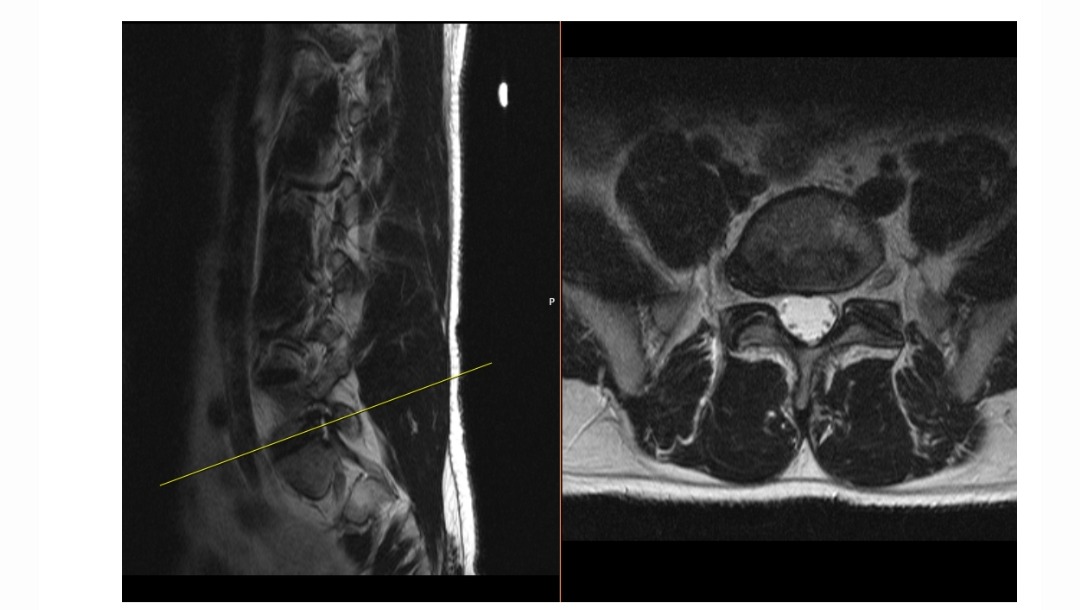

Here is the back story... in early April 2024, he had an MRI done on his back and shoulder.

With those MRI results, we were referred to Dr. Nicholas Andrade, Neurological Surgery for his back, and Dr. William Hobbs, Orthopedic Surgery for his shoulder.

At that time, we decided to go the non-surgical route for his back and just try the spinal injection.

On June 26, 2024, he had the epidural injection in his back with some relief.

On October 16, 2024, we saw pain management at Baylor Scott and White, and Sean received another similar epidural injection with not much relief.

We have an appointment scheduled for January 28, 2025, for a CT bone scan and a follow-up with Dr. Andrade in Tyler.

After this scan and follow-up, we will be getting surgery scheduled in Tyler.